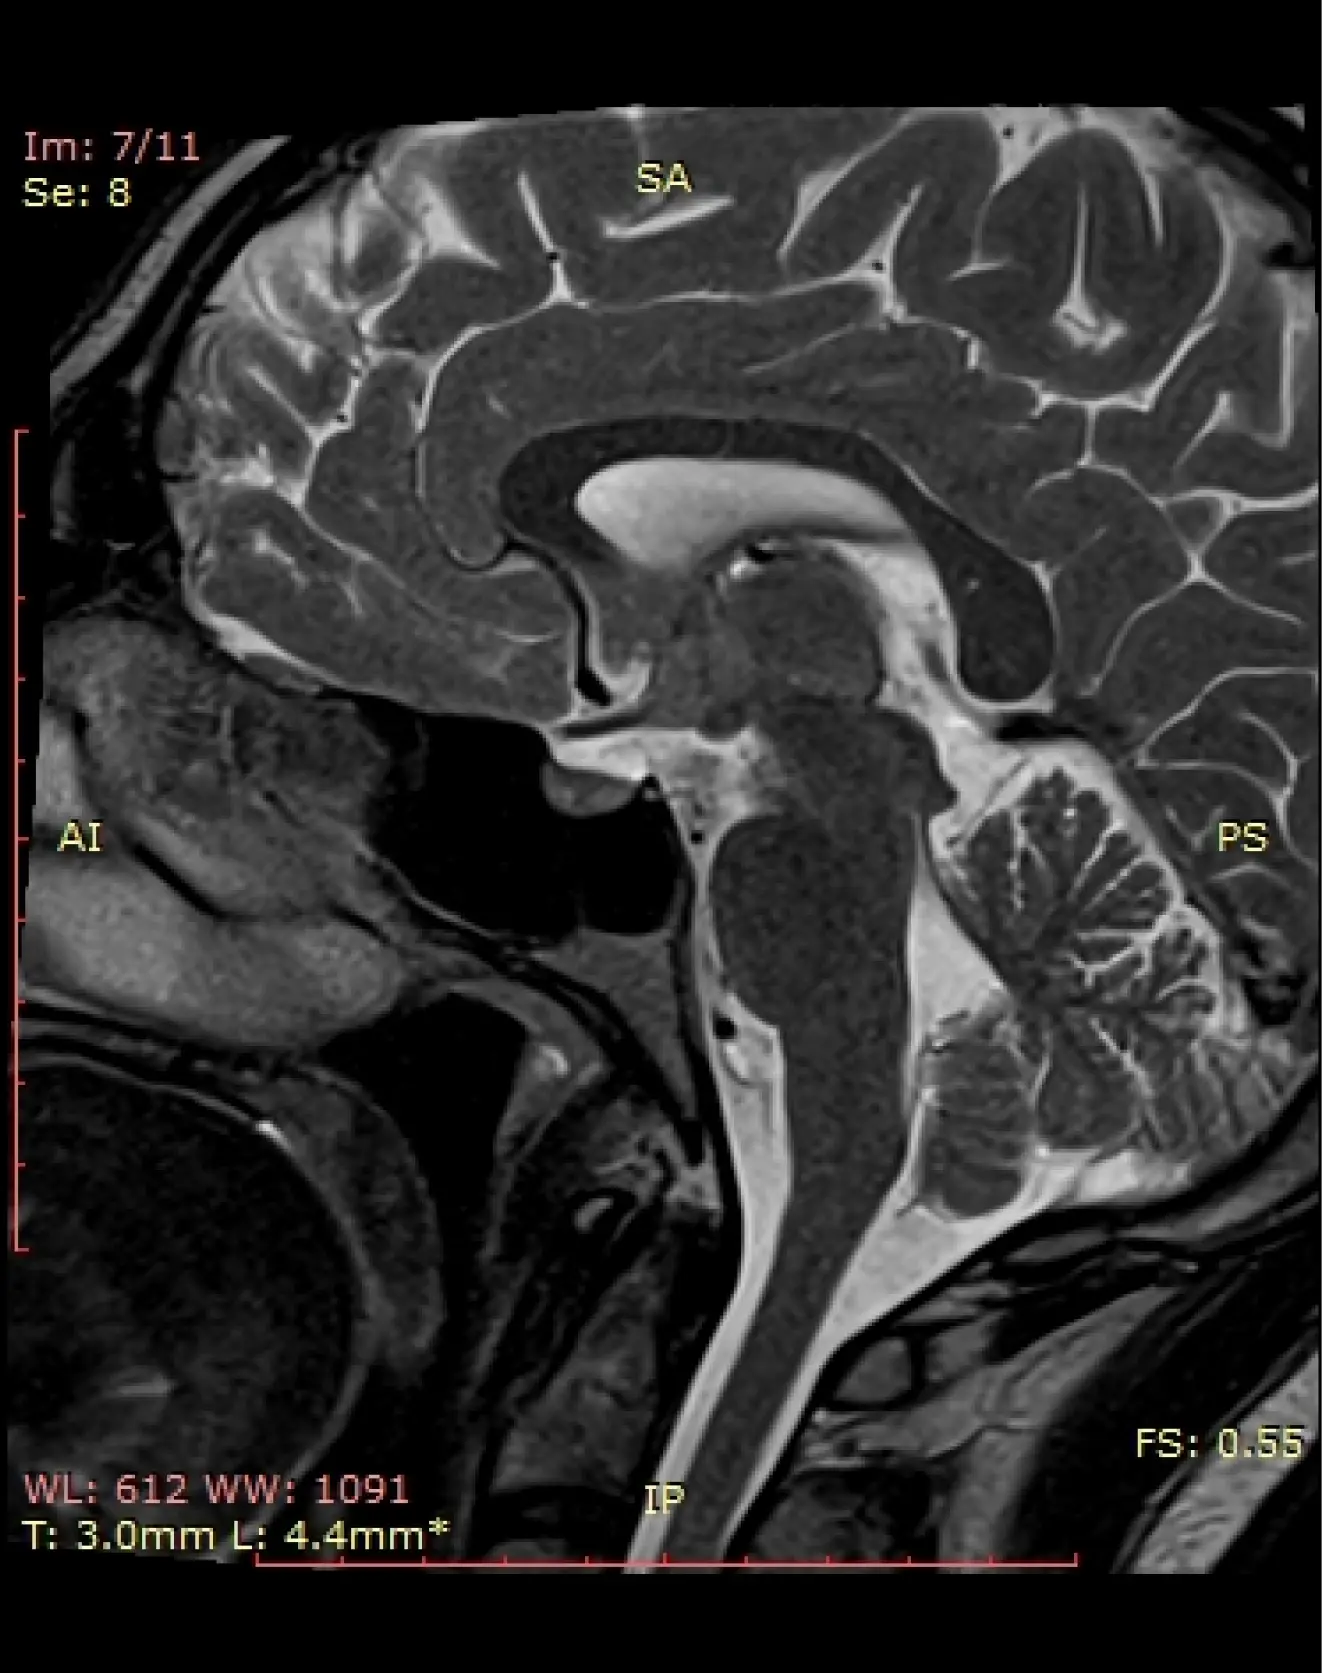

МРТ гипофиза (без контраста)

Исследование для выявления структурных изменений в гипофизе (микро, макроаденома, и т.д.), вызывающие гормональные нарушения.